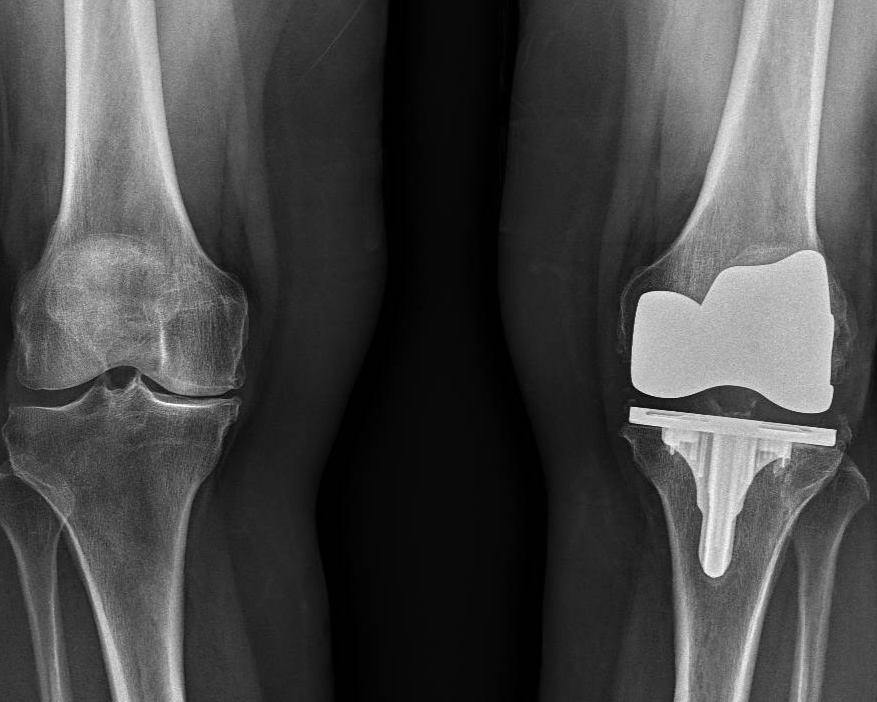

Total Knee Replacement

Total knee replacement (total knee arthroplasty) is a surgical procedure that replaces a damaged knee joint with an artificial one. This can significantly improve pain, function, and quality of life for people with severe arthritis or other knee conditions.